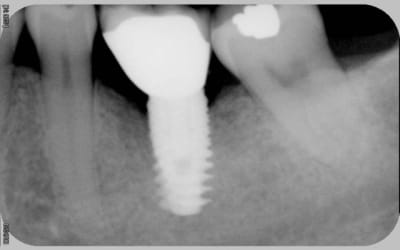

comme promis

voici les cas vus ce mardi (il me manquait encore 10 patients: sur les 5 autres, tout est ok)

ps: la carie et le tartre sur la 7 ont été traités